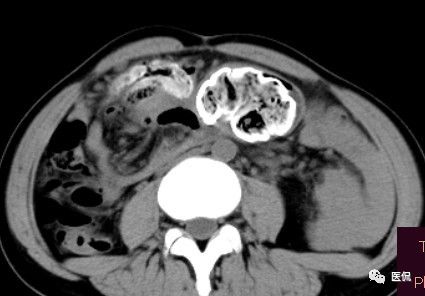

腹腔内残留的纱布在人体内引起渗出或液化坏死并纤维包裹形成异物性脓肿(纱布瘤)。纱布瘤的影像特点:圆形或卵圆形肿块,较大,有完整包膜,薄壁,较少的情况下为厚壁,边界较完整,增强后薄膜可以持续强化。不同时期的纱布瘤可以有不同表现:早期(10个月或半年内)多表现为蜂窝状;2~5年内一般表现为囊性飘带状;10~20年之后则为实性软组织密度,包膜钙化呈钙化网状结构。手术过程中残留在人体内的医用纱布所形成的肿瘤样病变。

纱布团遗留腹腔后,首先由大网膜及邻近肠管将其紧密粘连并包裹,自肠管与纱布团粘连处开始逐渐向周围扩展产生纤维结缔组织包膜直至完全包住纱布团,该包膜血管丰富,充血明显,随时间延长逐渐向纱布团网眼内生长,使包膜逐渐增厚。机体还通过在包膜内产生大量异物巨细胞来围歼异物纱线,使包膜内侧形成脓肿。当包膜完全形成后,肠管与纱布团的粘连变的疏松,此时纱布团具有了一定的活动度。

腹腔内遗留纱布团的影像学表现,以B超较具特征性,其主要表现为:腹腔或盆腔内特殊率减的黑色包块,后方伴有扇形衰减的声影,上窄下宽,好似一“黑色大布”,早期包块内含有不规则光团或光点,随时间延长有缩小或消失,为纱布团内气体。CT的优势在于早期常表现为软组织密度的肿块,其内可见多少不等的气泡,随时间的延长气泡逐渐被吸收减少至消失,增强扫描可见包膜不同程度强化而内容物无强化。熟悉其影像学表现,可在术前作出明确诊断。